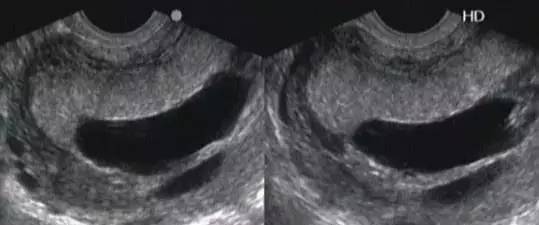

3、轮状 胎盘: ↑↑↑

发生率不到1/6000。指胎盘的胎儿面内凹,周围环绕增厚的灰白色环,环是由于双折的羊膜和绒毛膜构成的,其间有退化的蜕膜和纤维。蜷起增厚的羊膜绒毛组织常合并胎盘出血和梗死。可分为完全型(形成一完整的胎盘组织环,常与胎盘早剥、早产、IUGR、胎儿畸形、围生儿死亡率增高有关)和部分型(形成不完整的胎盘组织环,不引起任何胎儿异常)。

超声诊断:

a、特征性改变:胎盘边缘呈环状或者片状突向羊膜腔,内部回声与胎盘实质回声相似,有出血或者梗死者内部可出现无回声或者低回声区。

b、探头对胎盘做放射状扫查,有利于评估轮状胎盘的程度。